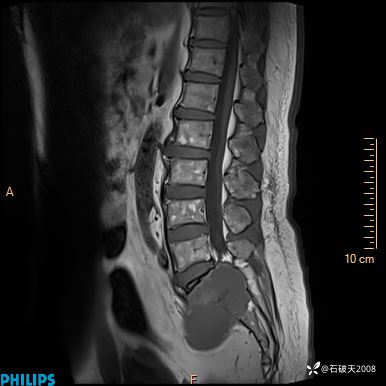

2023年3月份MRI影像

T1矢状位